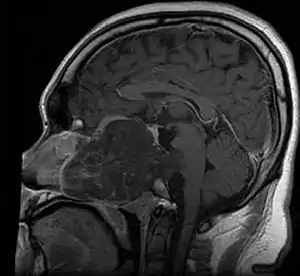

MRI of extensive clival chordoma in 17-year-old male patient, axial view. Tumor in the nasopharynx extending from nasal cavity to brainstem posteriorly is clearly visible. | |